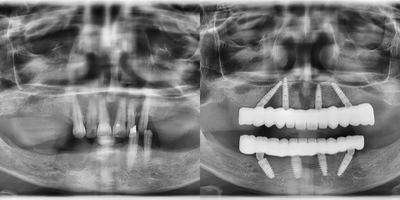

55-64 year old woman treated with All-on-4 Dental Implants, Dental Implants

Our patient had severe bone loss and hopeless remaining teeth. We have performed extraction of hopeless teeth and All-on-4 implants for both jaws. After a 3 months of osseointegration period, we delivered her screw-retained fixed prosthesis.